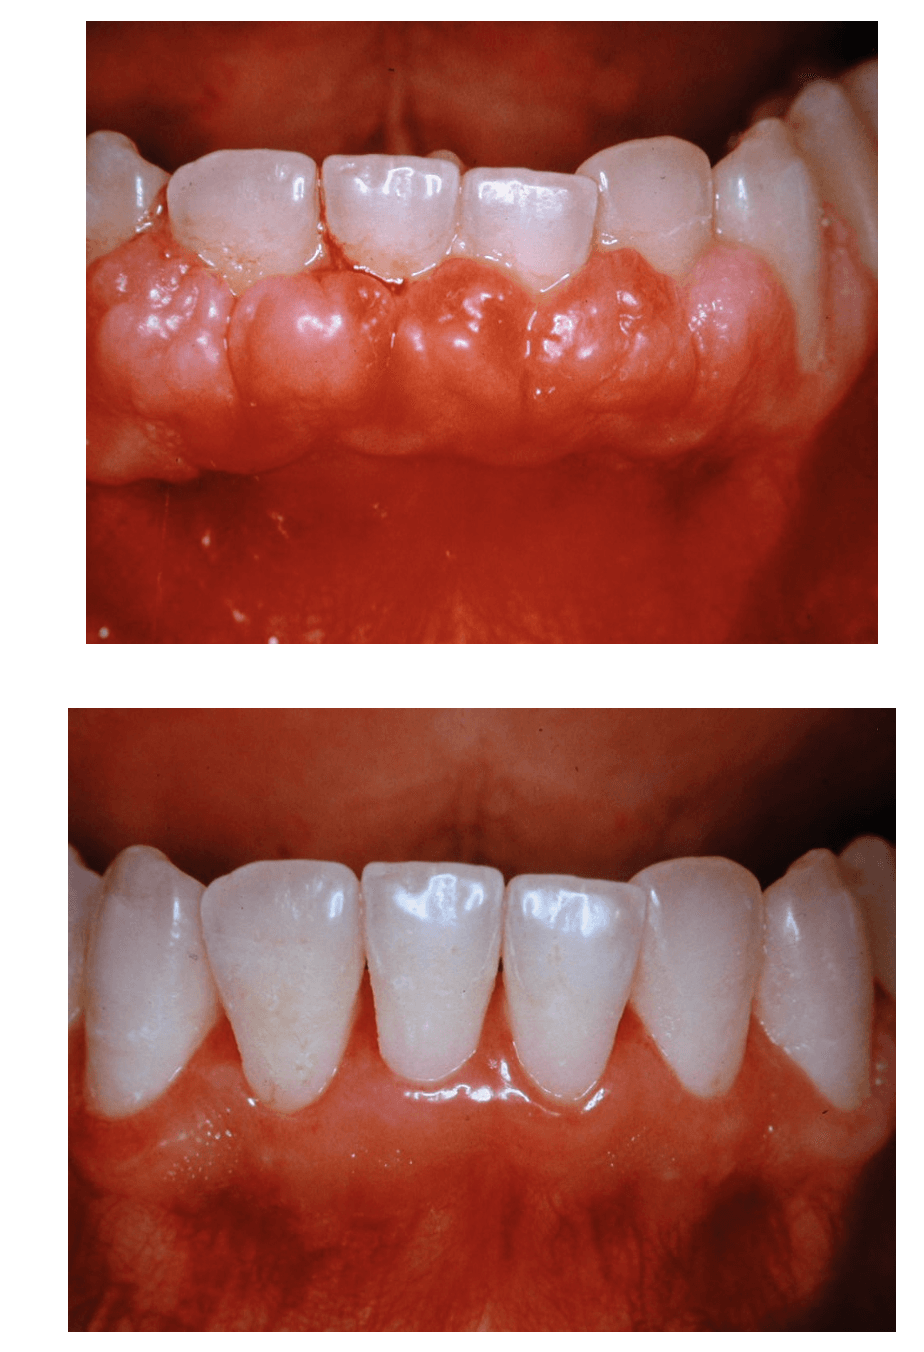

La malattia gengivale è un processo infiammatorio caratterizzato da un accentuato arrossamento, da gonfiore e sanguinamento della gengiva. La forma iniziale è la gengivite, un’infiammazione delle gengive causata da un accumulo di placca batterica. Se il paziente non osserva le manovre corrette di igiene e i controlli professionali, essa può progredire fino ad una condizione grave in cui il processo infiammatorio si estende in profondità fino all’osso di sostegno: la parodontite.

Questa patologia rappresenta una delle cause della perdita di tessuto connettivo, del riassorbimento dell’osso alveolare e della formazione di tasche parodontali che possono condurre alla perdita dei denti ed è una delle cause più comuni della perdita dei denti negli adulti. Grazie alla chirurgia orale per queste tipologie di malattie infiammatorie che colpiscono il tessuto di sostegno del dente, vengono eseguiti dei trattamenti parodontali come il curettage ( ossia il procedimento di rimozione del tartaro o della placca dalla parete orale al di sotto della gengiva) o la levigatura delle radici a cielo aperto, o ancora interventi definiti rigenerativi per l’aumento dello spessore osseo, innesti gengivali, rimozioni di cisti dentali o tumori del cavo orale. Questa tipologia d’intervento consente di ricostruire il tessuto danneggiato o perso e può avvenire in contemporanea all’intervento implantare (rigenerazione ossea perimplantare) o prima di effettuare l’intervento stesso ( rigenerazione ossea preimplantare). La rigenerazione ossea può avvenire in due modi: tramite l’auto trapianto osseo, ossia il prelievo dell’osso da una parte del corpo del paziente e l’innesto nella gengiva, oppure si procede con l’applicazione di osso artificiale, realizzato in materiale sintetico e biocompatibile, che istallato nella gengiva e ricoperto da una membrana riassorbibile, si integra perfettamente con l’osso. Il nostro studio medico dentistico, grazie alla consolidata collaborazione con il dipartimento di parodontologia della facoltà di Odontoiatria dell’Università “La Sapienza “ di Roma e alla comprovata esperienza nel campo implantologico e parodontale è in grado d’intervenire con entrambe le modalità, garantendo al paziente la massima efficienza